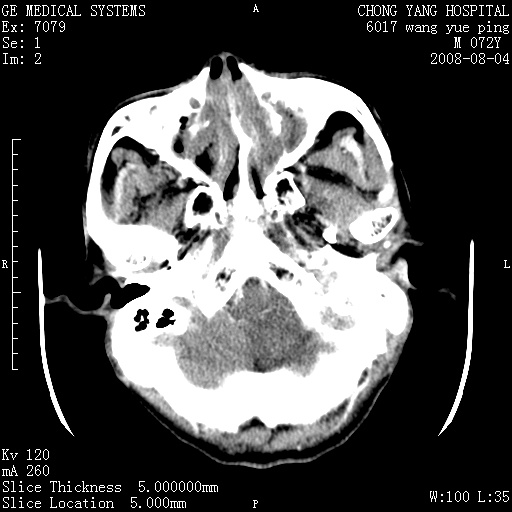

标题: CT14987:M72Y,头痛头昏,BP220/110. [打印本页]

标题: CT14987:M72Y,头痛头昏,BP220/110.

1)考虑左侧小脑脑梗塞。2)脑白质病。3)脑萎缩。4)双侧鼻腔新生物(息肉?)并阻塞性副鼻窦炎。

1)考虑左侧小脑脑梗塞。2)皮脑。3)双侧鼻息肉并阻塞性副鼻窦炎。

1\\考虑左侧小脑脑梗塞,脑白质病。2\\ 双侧鼻腔新生物(息肉?)并阻塞性副鼻窦炎。

另:脑白质病。脑萎缩。双侧鼻腔新生物(息肉?)并阻塞性副鼻窦炎。

考虑小脑梗塞,鼻腔息肉,老年脑改变。建议mri明确

1)考虑左侧小脑脑梗塞。2)脑白质病。3)脑萎缩。4)双侧鼻腔新生物(息肉?)合并副鼻窦炎。